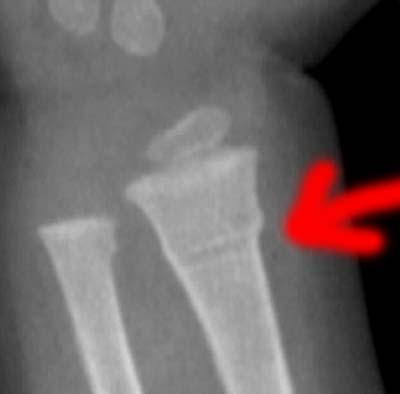

Ulna Break